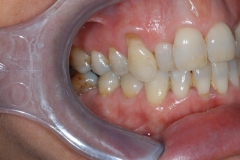

This patient experienced many areas of gum recession, primarily on the upper and lower front teeth. This patient's own tissue was used to correct the problem.